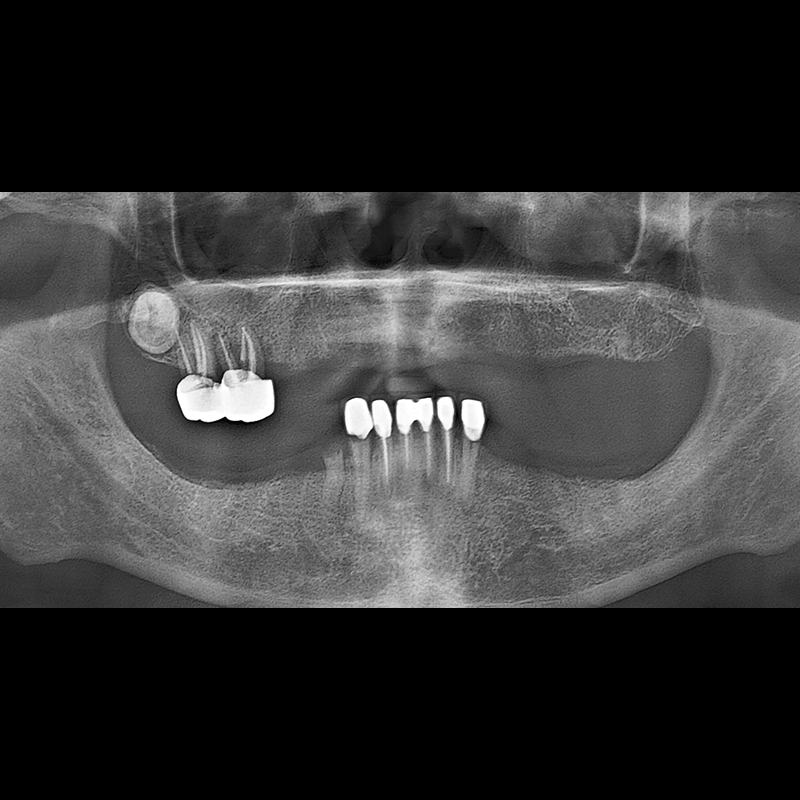

BEFORE AFTER

インプラント手術事例 2025.05.30

欠損した歯の部分と、生かしにくい歯の位置にインプラントを植立しました。